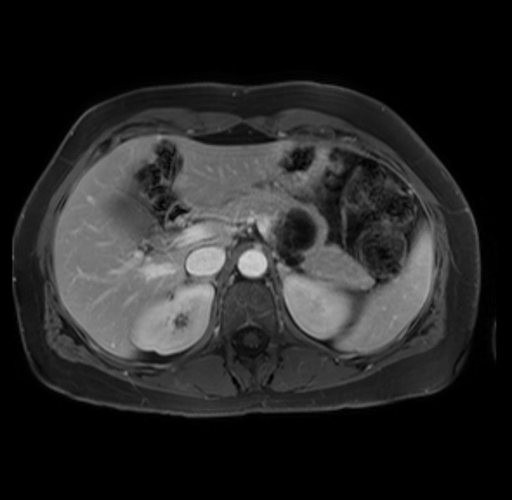

Imaging Analysis

Look through the patient's CT scan to identify any areas of concern for the necessary procedure.

Based on your CT findings, which issue(s) are present and would give reason for "planned slowing down moment(s)" in this case?